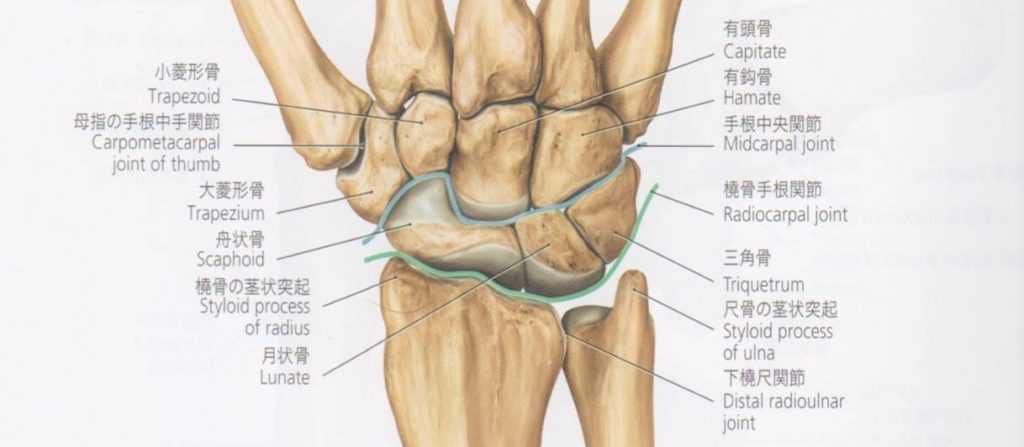

僧帽筋切除術では、外科医は僧帽筋と呼ばれる手首の付け根の骨を切除します。台形は小さな骨で、最大直径が 1 インチ未満です。 CMC 関節形成術では、除去された骨が人工インプラントに置き換えられます。

- その後、外科医は僧形骨を除去し、インプラントと置き換えます。

- 靱帯再建:損傷した靱帯の一部を、別の結合組織片から作成した移植片で置き換えます。

- 癒合(関節固定術):プレートまたはネジを使用して、僧形骨を親指の付け根の長く細い骨に癒合します。

- 僧帽筋切除術:僧帽筋の骨を外科的に除去します。

- 靱帯の再建と腱の挿入:関節を構成する骨の損傷した表面を軟組織で置き換えて、骨を分離した状態に保ちます。